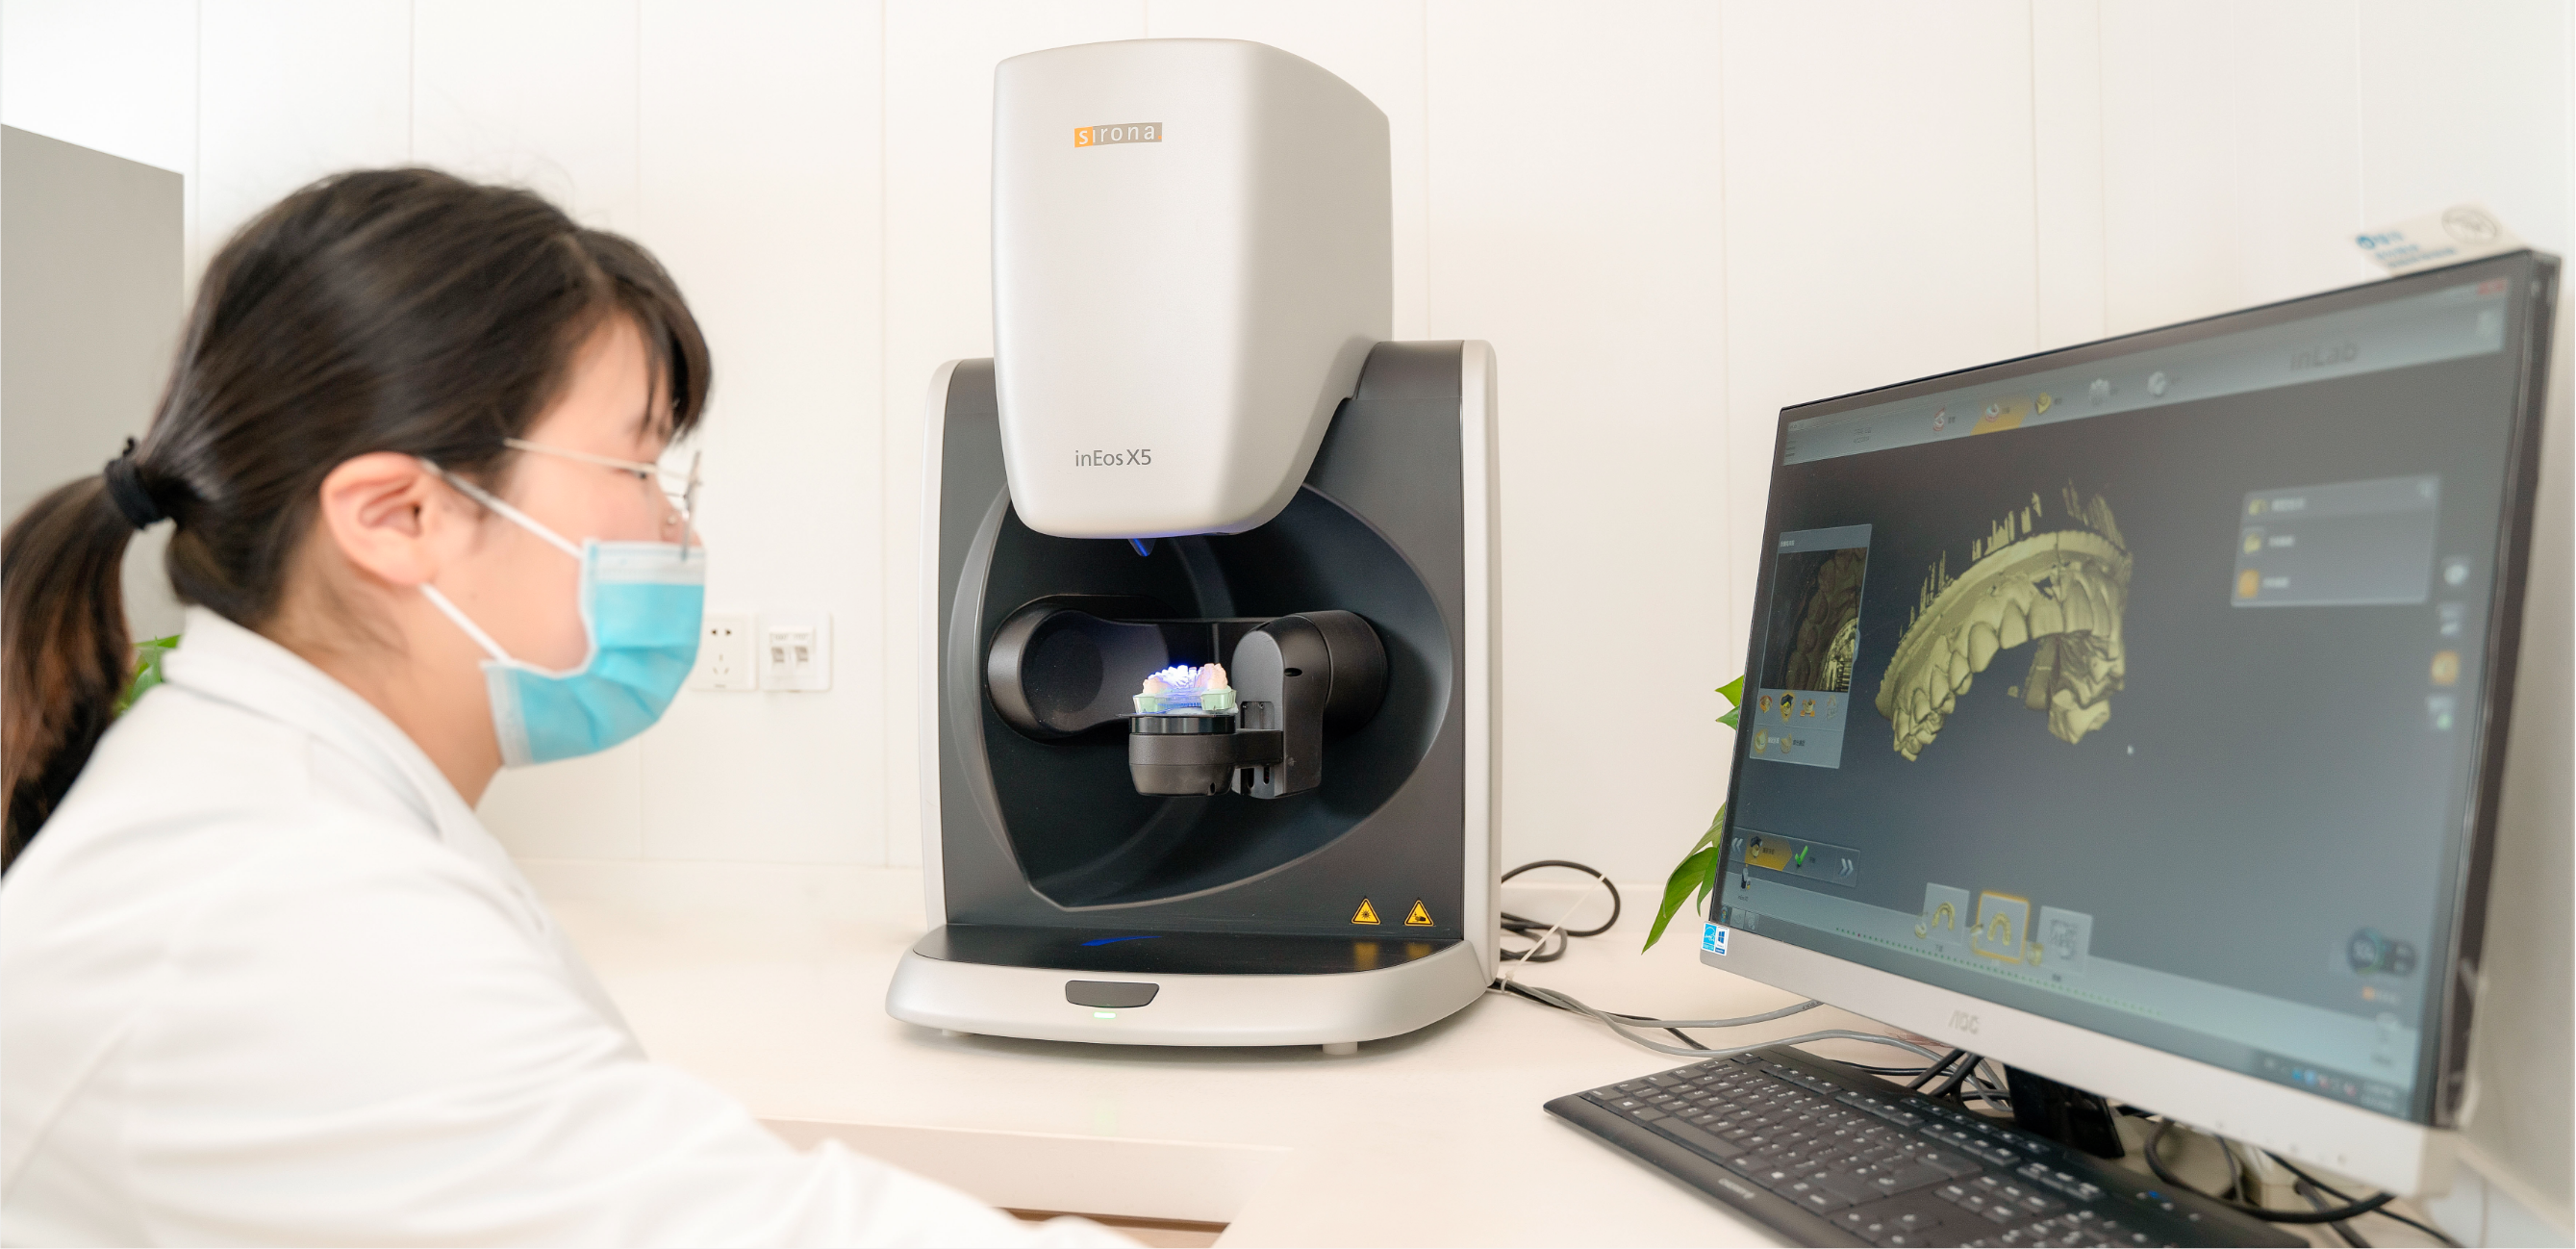

数字化加工学科

DIGITAL PROCESSING

兔博士口腔医疗科技集团数字化加工,突破了几十年的口腔义齿加工临床操作方式,特别是口腔扫描、修复体设计软件和数字化制造技术水平的大幅度提升,大大地缩短顾客就诊及戴牙时间。兔博士口腔医疗科技集团数字化加工学科有自己的义齿加工中心,在医生进行取模后,专业的义齿加工技师将在先进的义齿加工设备协助下,在数小时内出色的完成加工,真正做到当天看牙当天戴冠,实现顾客“即刻美牙”的梦想。